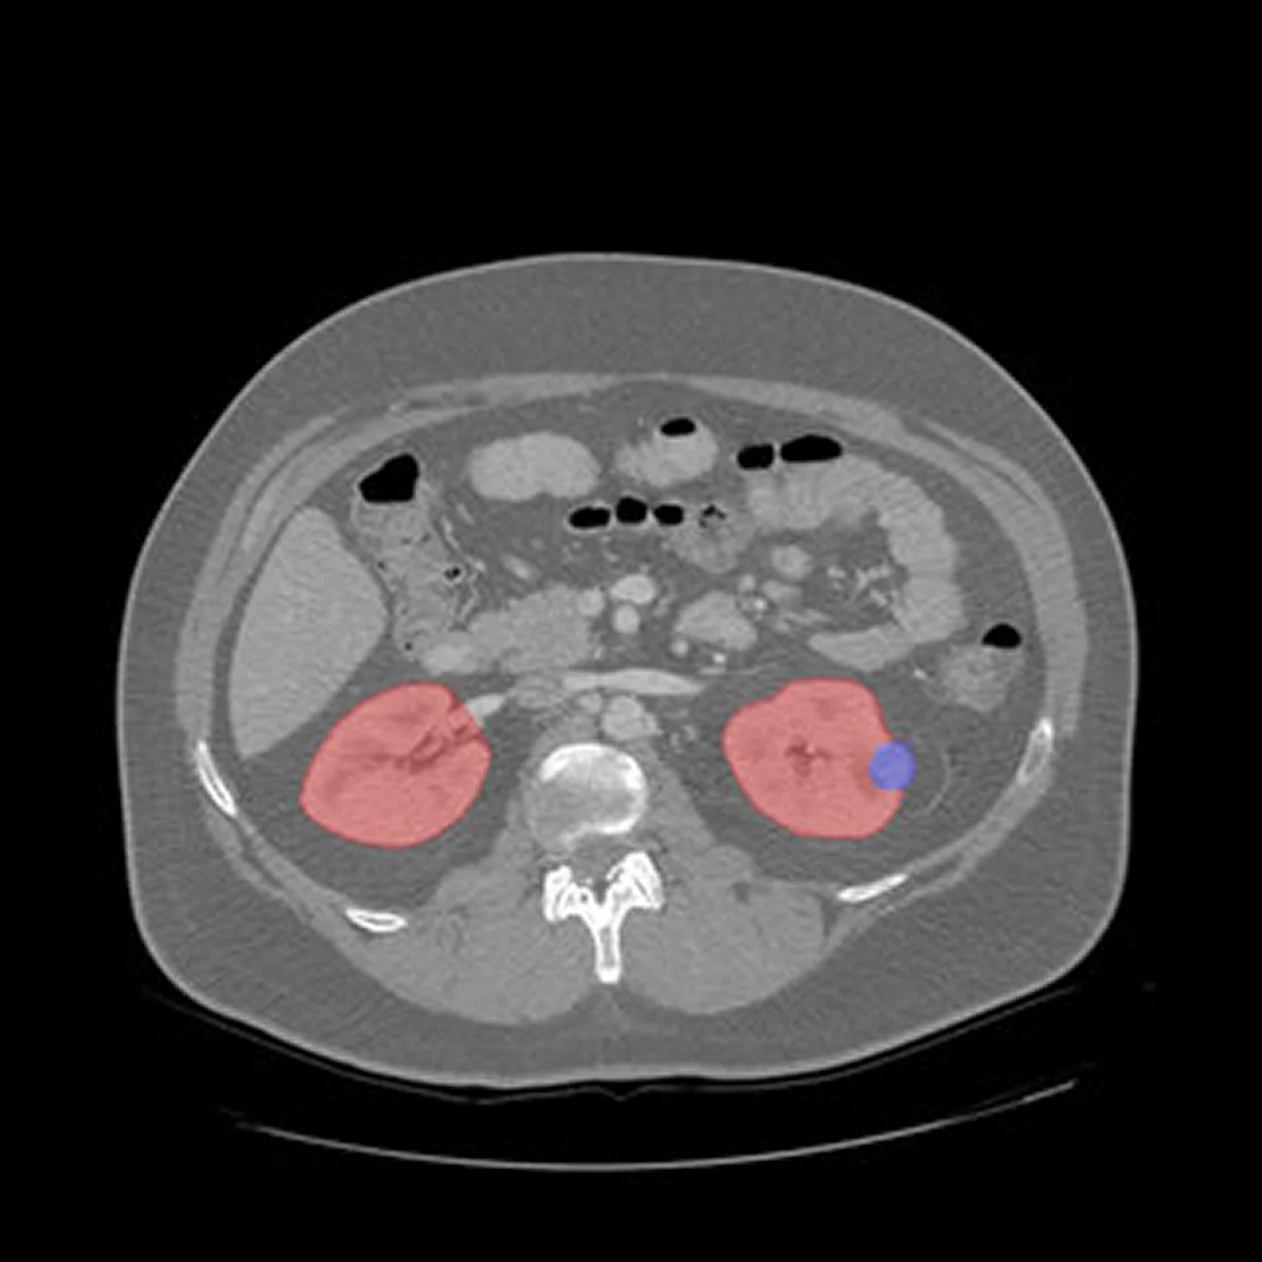

Medical image segmentation

Medical image segmentation</b> is the process of partitioning medical images such as CT, MRI, PET, or ultrasound scans into meaningful regions that represent organs, tissues, or pathological structures. This step is essential for medical image analysis, enabling clinicians and algorithms to isolate regions of interest , quantify abnormalities, and enhance diagnostic precision.

Medical AI segmentation, accurate labeling and delineation ensure that deep learning models can identify diseases, detect anomalies, and support automated diagnostic workflows with reliability and consistency.